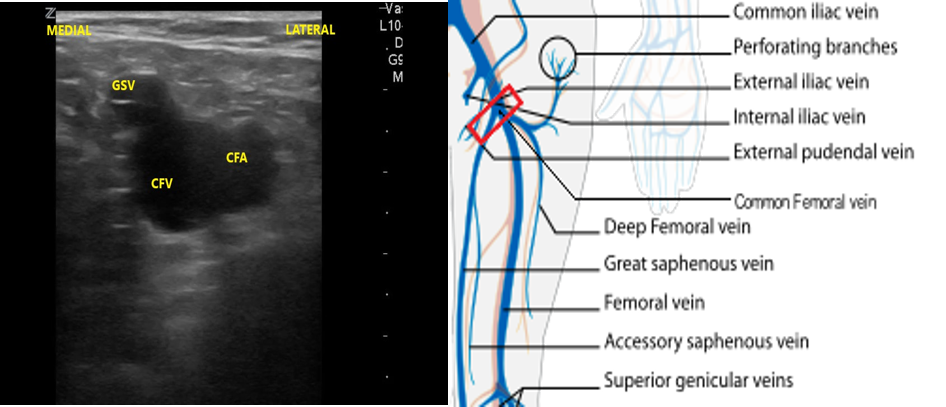

- The first venous confluence is the great saphenous vein (GSV) and common femoral vein (CFV). The GSV joins the CFV medially.

- Slide the transducer distally 1 to 2 cm to the junction of the CFV and GSV ( 10 and 11) and compress.

- Figure 10. Junction of the CFV and GSV 1-2 cm below the inguinal canal with transducer orientation indicated (red rectangle).

- Figure 11. Compression of the CFV at the junction of the GSV 1-2 cm below the inguinal crease.